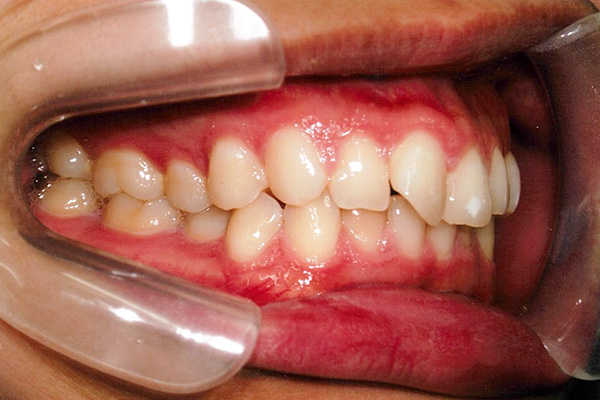

治療前